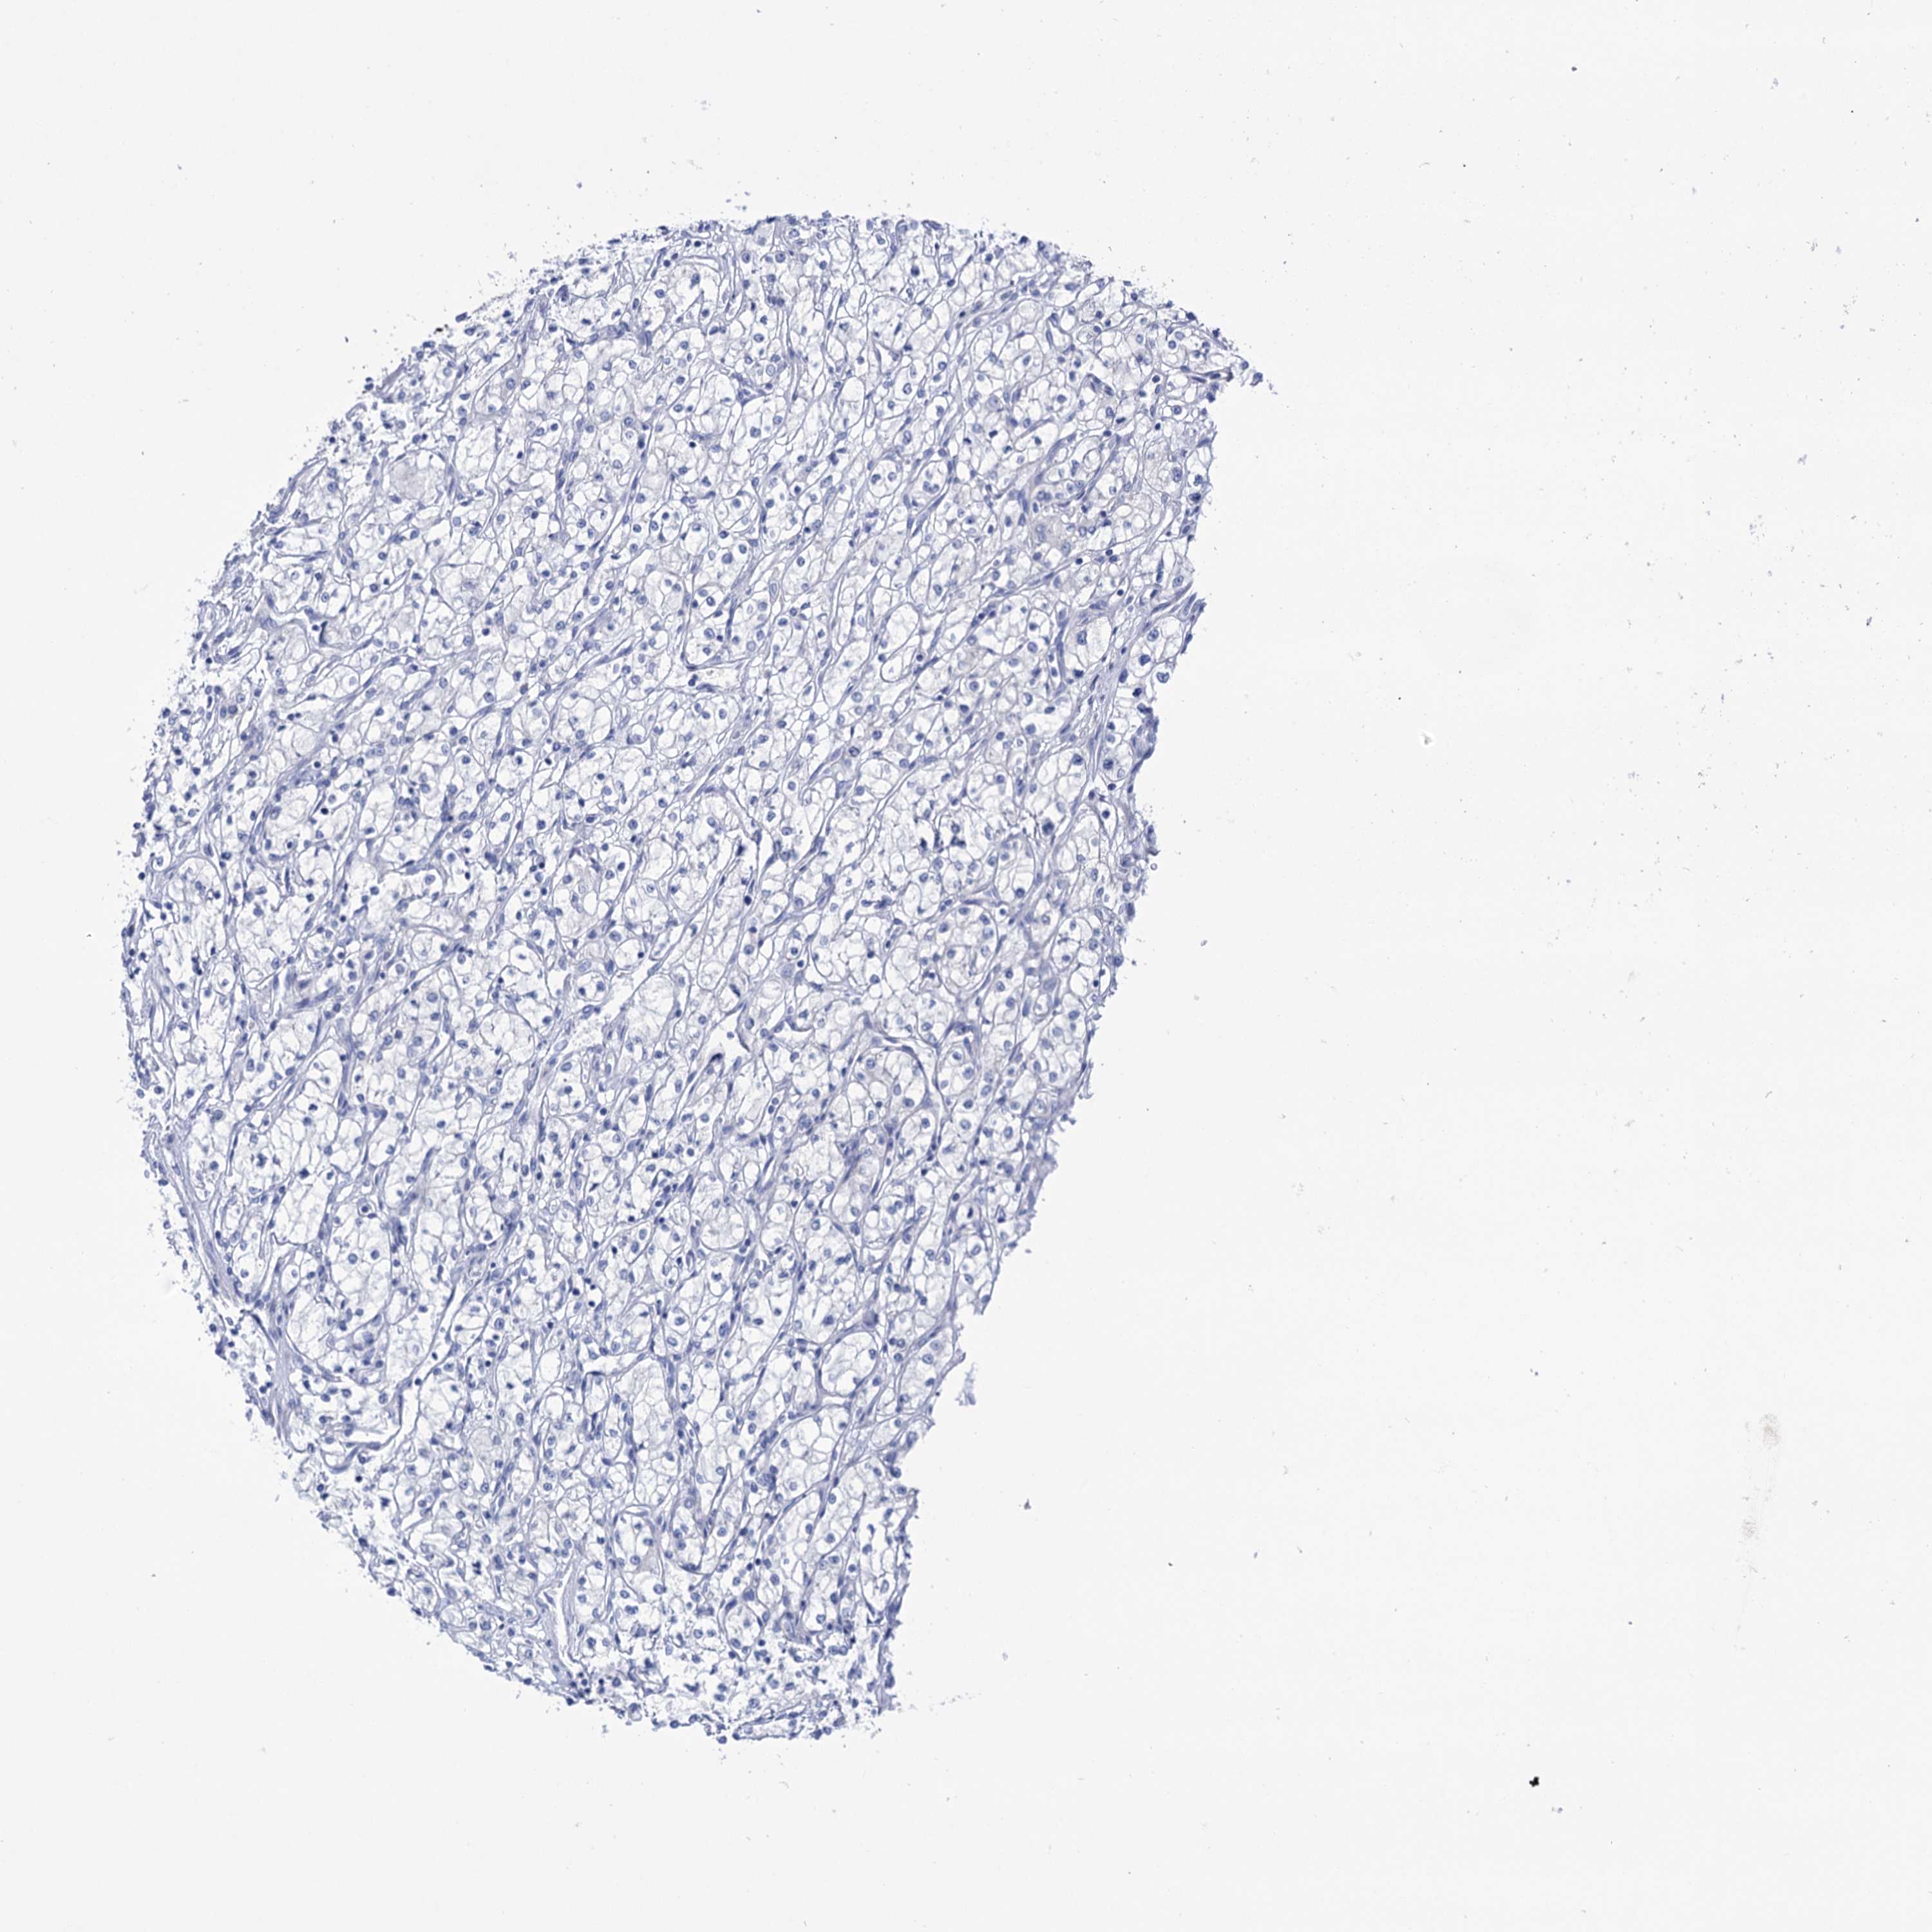

CANCER RENAL CANCER Show tissue menu

KICH TCGA KIRC TCGA KIRC VALIDATION KIRP TCGA PROTEIN RCC CPTAC PROTEIN EXPRESSION